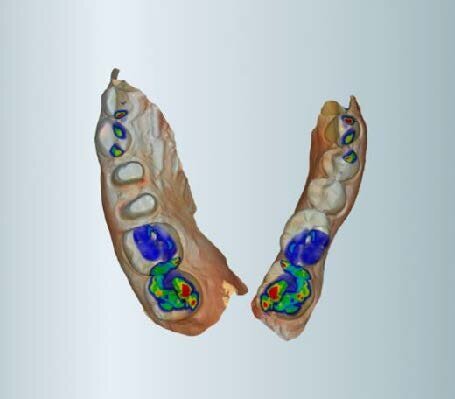

Fig. 6: Software proposal of crowns

After correlating the models with the software, we started tracing the margins. Moreover, after the definition of the insertion axes, MyCrown Software gave us its design proposal of the crowns. Obviously, software proposal of the crown design is based on the anatomy of the other teeth of the patient. This does not prevent us from modifying the tooth anatomy based on the neighbor and antagonist teeth.

Later on, after checking the contact points with the neighbor teeth and the occlusal contacts with the antagonists, we were able to proceed with the manufacturing phase. Once the milling process was over, we moved on to polishing and painting of the brand new crowns, in order to make them look like real teeth.